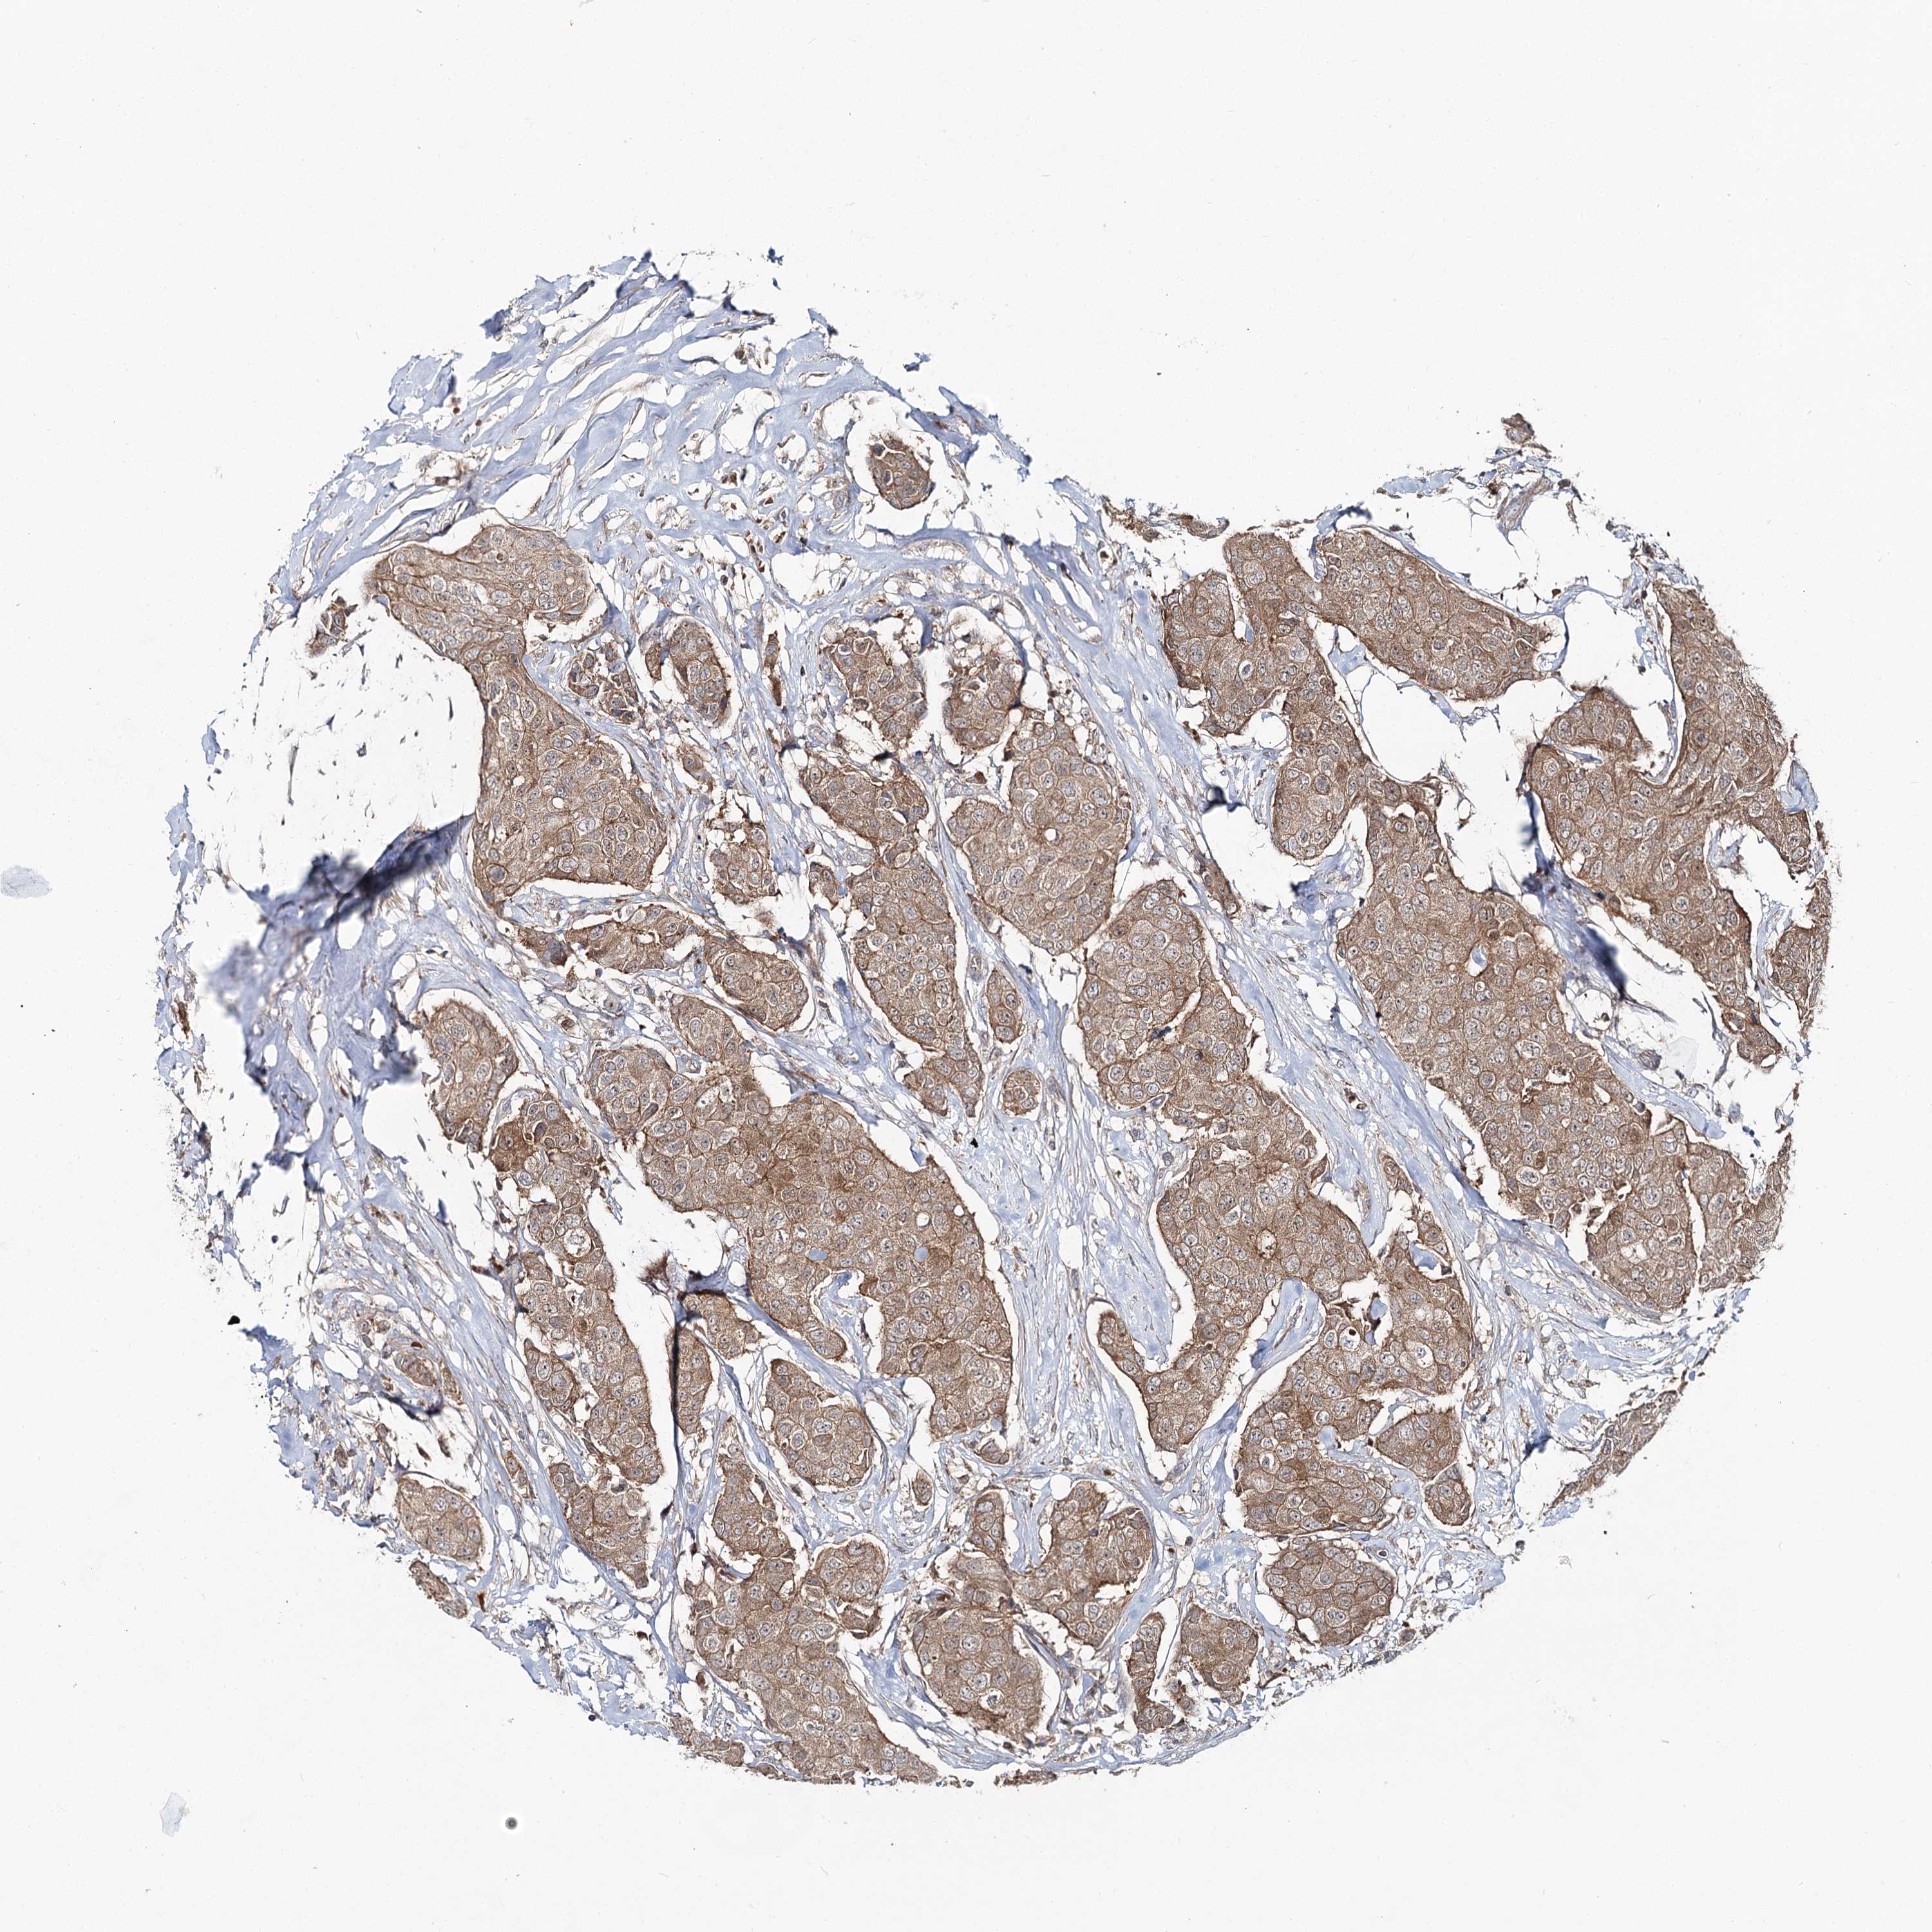

CANCER BREAST CANCER Show tissue menu

BRCA TCGA BRCA VALIDATION PROTEIN EXPRESSION